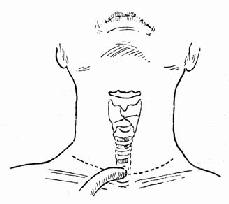

4.手术方法 ①颈部低位横切口行常规气管切开术(图96-10)。②常规喉裂开术(图96-11)。直视下仔细缝合喉粘膜裂口(96-12)。置入事先准备好的喉扩张模(牙模胶或硅橡胶制成)放入喉腔,扩张模下界在环状软骨水平,上界在室带水平即可,用金属线固定此扩张模。金属线穿过甲状软骨板和皮肤后,用钮扣固定在颈部皮肤表面(图96-13)。尽量对合复位甲状软骨板,并缝合甲状软骨板外软骨膜,逐层缝合切口(图96-14)。③手术后使用强有力的抗生素控制感染。按气管切开术后护理。④6~12周后直接喉镜下取出喉扩张模。⑤取模后试行堵管,无呼吸困难后可拔除气管套管。

图96-10 颈部低位横切口气管切开